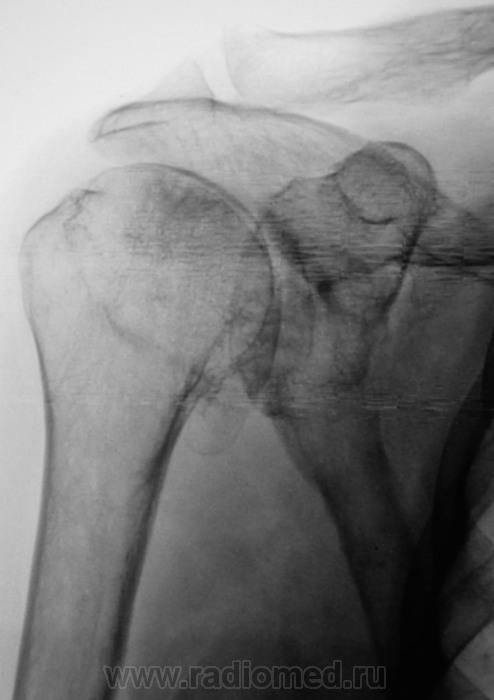

Смущает дополнительный "контур" по стрелкам.

Думаю,что это "неодокостеневшие" костные разрастания(не знаю,как точно обозвать).

Что в анамнезе? Была травма? После чего боли появились. Что можно сказать об объёме движений? Мне кажется, что изменения связаны с обызвествлением суставной сумки.

Мне кажется, что изменения связаны с обызвествлением суставной сумки.

Мне тоже так показалось.

Для оценки состояния хрящевой губы МРТ

А может быть для начала УЗИ? Пока она до МРТ доедет. Есть такое понятие "замороженное плечо". Возможно оно, вот узнать бы объём движений.

Вот, вот, пациентка так и говорит, что как бы плечо замерзло. Объём движений пациентной оценивается, как нормальный, но боли мешают...